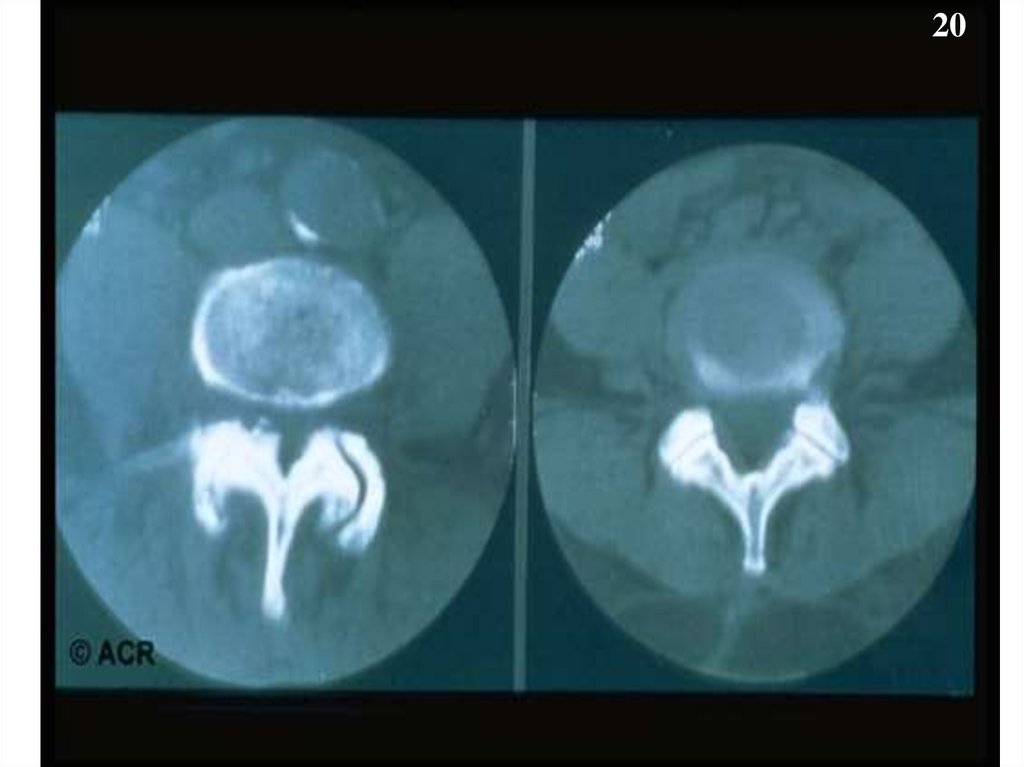

20.

20